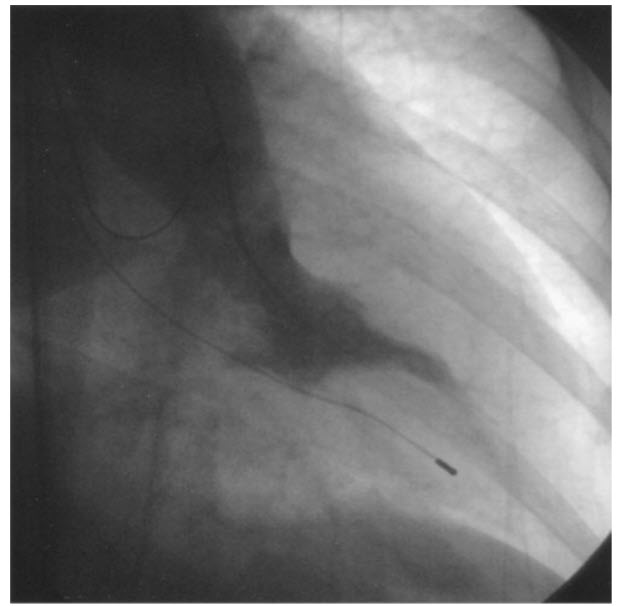

Match the following cardiac catheterization still-frame slide to it's respective diagnosis.

Hypertrophic cardiomyopathy. A left ventriculogram in right anterior oblique projection demonstrates a small ventricle with marked ventricular hypertrophy and narrow left ventricular outflow tract (LVOT).